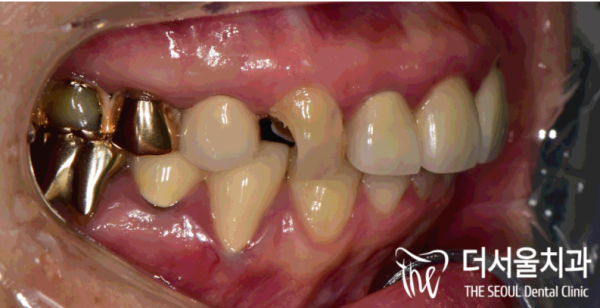

이 환자분은 오른쪽 송곳니가 파절되는 손상이 생기셔서

급하게 성남치과 더서울치과를 찾아주셨습니다.

이 환자분의 경우에는 충격을 받은것은 아니고

심한 충치로인해 치아가 부식되었고, 이를 방치한 결과

이렇게 치아가 파절되게 된 것으로 보입니다.

This patient has damage to his right fang

He urgently visited Seongnam Dental Clinic The Seoul Dental Clinic.

In this patient's case, he wasn't shocked

The teeth were corroded by severe cavities, and as a result of neglecting them

It seems that this is how the teeth are broken.